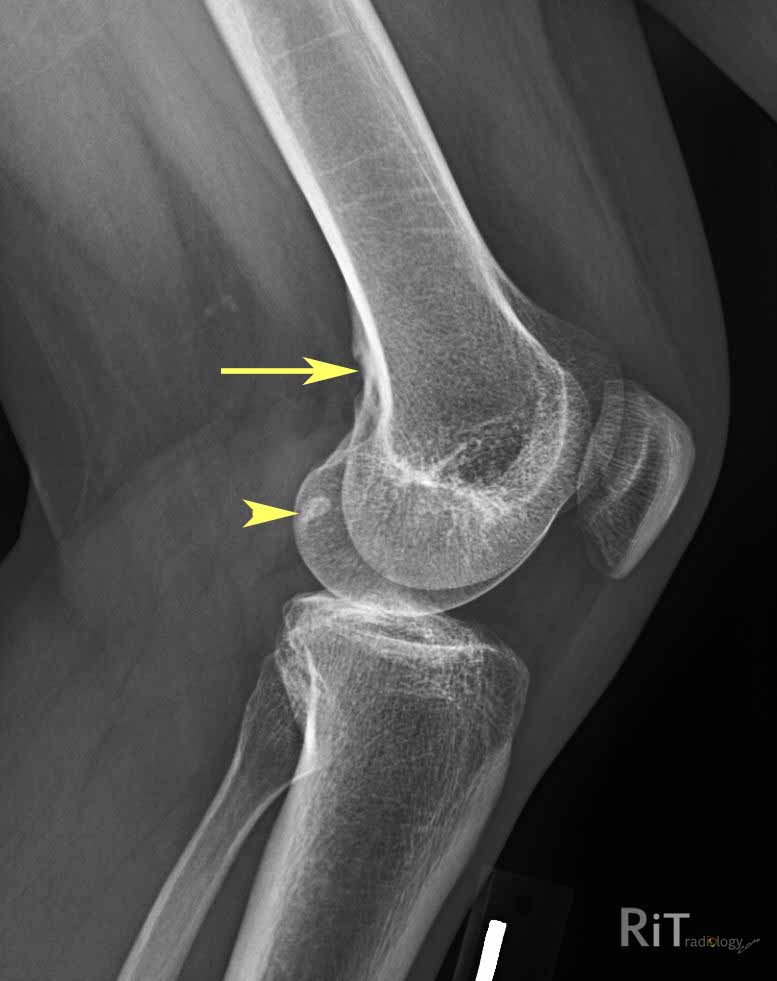

Строение и роль сесамовидной косточки в коленном суставе